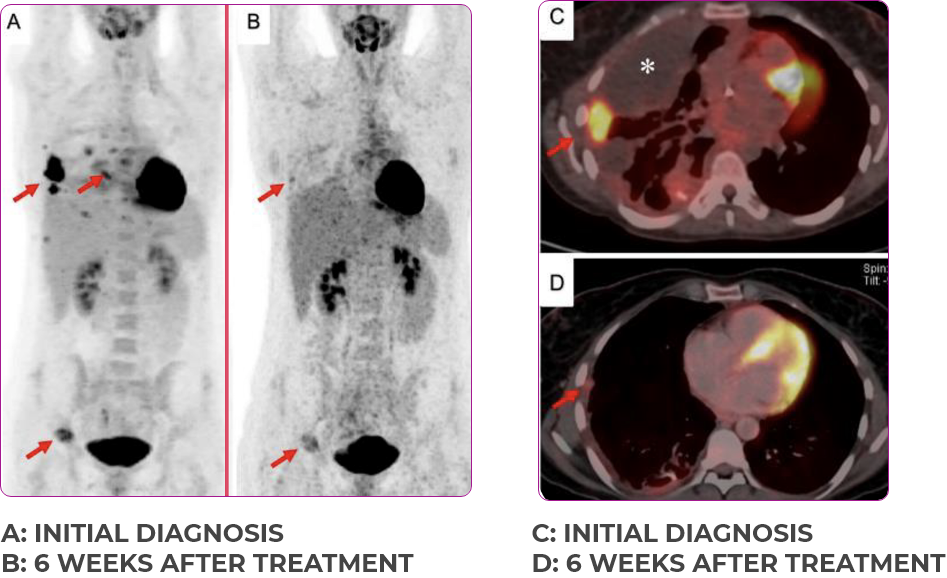

PATIENT CASE:

METASTATIC NSCLC1,a

- 30-year-old female

- Progression on first-line doublet chemotherapy

- PRa after 6 weeks of treatment with VITRAKVI® (larotrectinib)

- Complete clinical response achieved by 12 months with residual scarring

Response to VITRAKVI1

- Partial response and symptom improvement confirmed by chest X-rays after <1 month of treatment

- Imaging performed 6 weeks into treatment revealed considerable decrease in the size of both target lesions

- No treatment-related AEsa were reported

- Patient was symptom free and remained on VITRAKVI

Response in primary and metastatic lesions1

Lung imaging of primary tumors.

SCAN 1: LUNG

SCAN 2: LUNG AND BONE